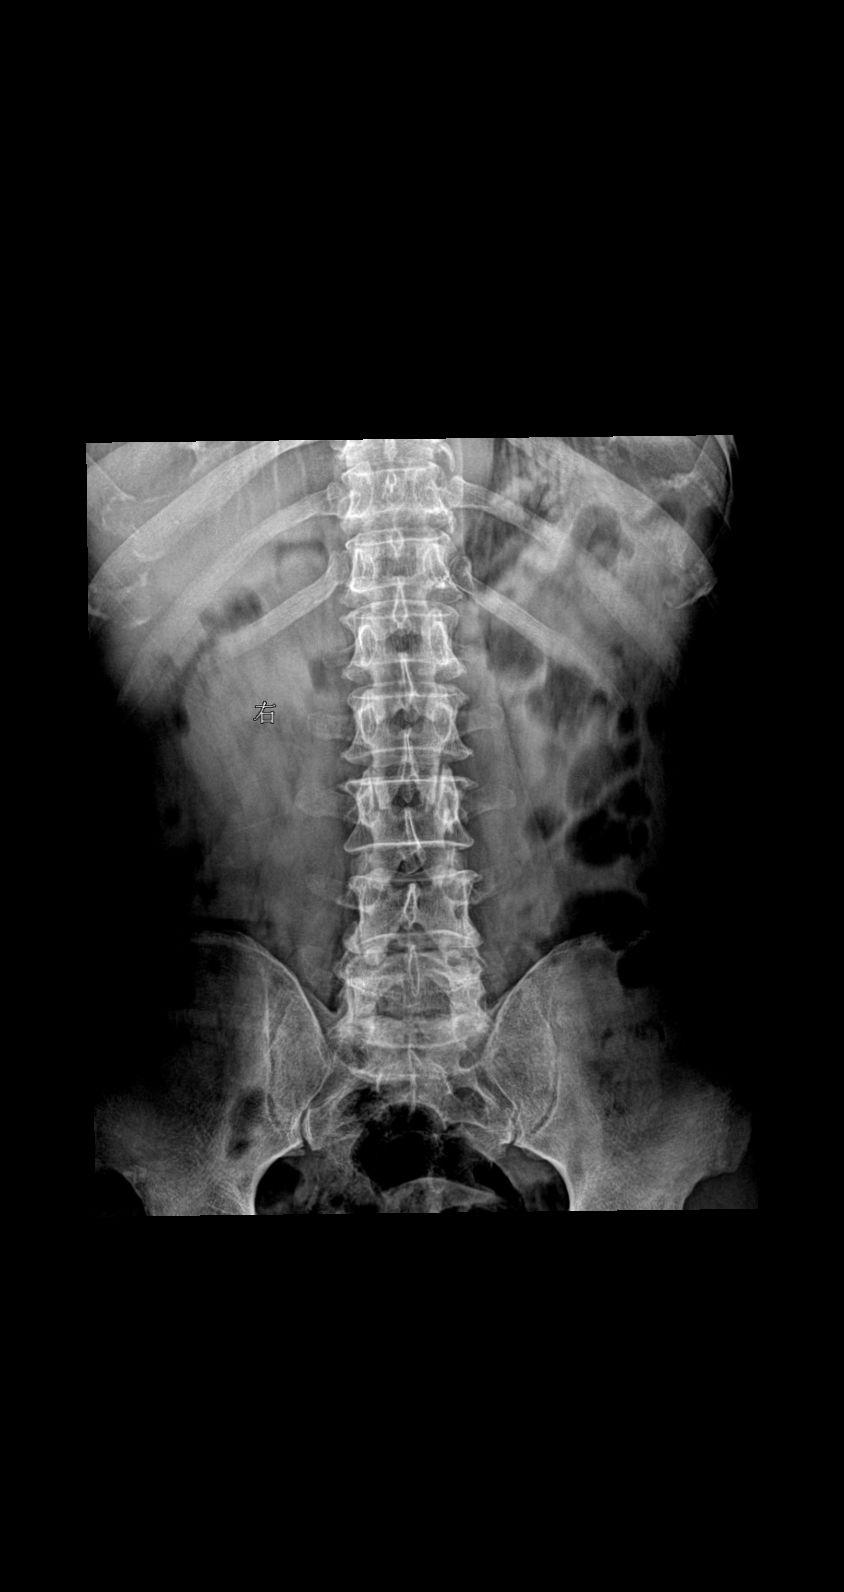

男 55 腰部疼痛就诊